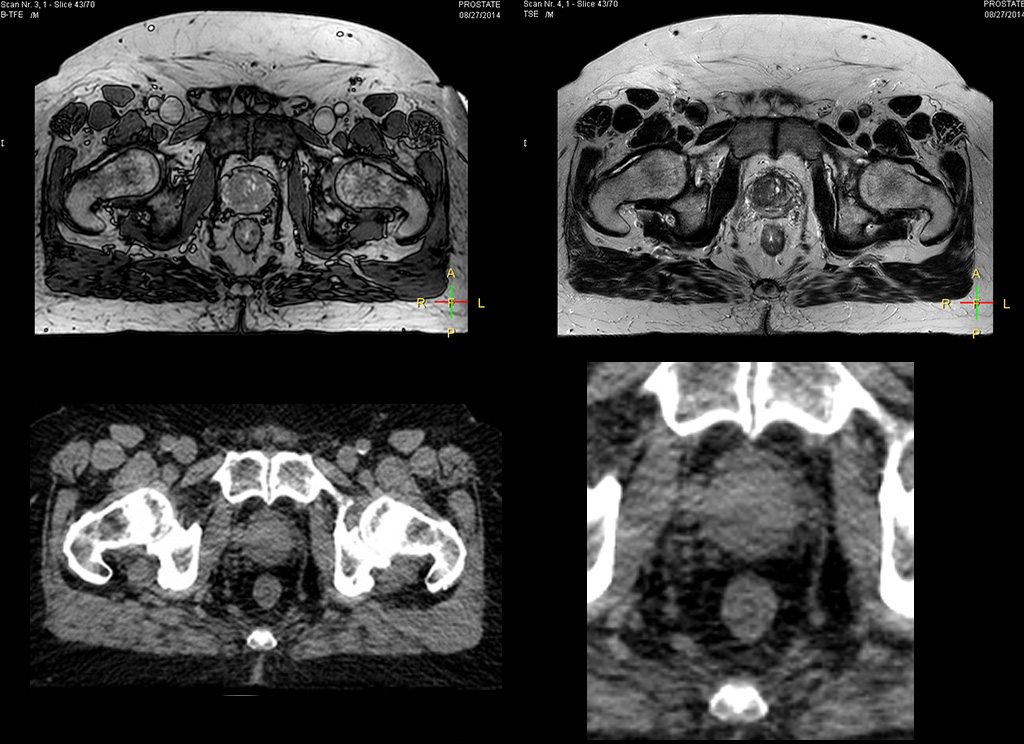

“We currently use MR-RT mainly in the abdomen and pelvis region: prostate, colorectal, pancreatic, cervical, and liver. Also in the brain, we are starting to use it,” says Dr. Yan.

Impressive clinical benefits for prostate

“The biggest problem for CT-based planning, especially in prostate, is you can’t see the cancer very well,” says Dr. Stevens. “On CT it can be quite challenging to see the edge of the prostate especially at the apex. When the edge of the prostate can’t be delineated well on CT, radiation oncologists will increase their margins a little bit so they don’t miss it, but that can also increase toxicity.”

“Using MR, the prostate is well delineated. We quickly see the edges of cancerous tumors like in prostate cancer, and as normal structures can be defined, we can optimize the treatment plan to protect these organs and their normal function. This can potentially improve the outcome. And it improves workflow as well. We can contour more quickly, confident that the tumor is going to be in the field.”

“The Ingenia 3.0T MR scanner provides high resolution allowing us to make scans fast for the patients. It also gives the potential to include methods like MR spectroscopy and diffusion weighted Imaging, which we’re in the process of doing right now,” Dr. Stevens adds.